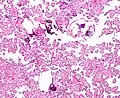

Histopathology

The tumor is neuroectodermal in origin and similar in structure to a normal choroid plexus. They may be created by epithelial cells of the choroid plexus. Papillary fronds lined by bland columnar epithelium are visible under the microscope. Normal absences include mitotic activity, nuclear pleomorphism, and necrosis.[10] Tumors have positive immunohistochemistry for cytokeratin, vimentin, podoplanin, and S-100.[11] Up to 20% of choroid plexus papilloma patients may test positive for glial fibrillary acidic protein (GFAP).[12] Studies have found that fourth ventricle cancers express more S100 than lateral ventricle tumors, and older patients (over 20 years) express more GFAP and transthyretin than younger patients.[13] Some individuals with choroid plexus papilloma have germline TP53 gene mutations, according to genetic analyses.[14] These cancers rarely exhibit nuclear p53 protein positivity. Aicardi syndrome, hypomelanosis of Ito, and 9p duplication are syndromic correlations of choroid plexus papilloma.

Micrograph of a choroid plexus papilloma. H&E stain. -

Plexuspapillom Detail -

Plexuspapillom Overview